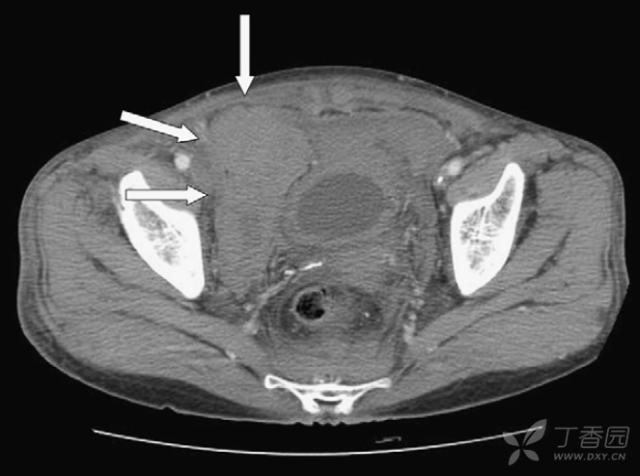

入院第二日早晨,全腹CT增强扫描提示:腹腔积液,盆腔血肿(箭头所指:10*5.7cm,较入院时增加);

右侧腹膜后巨大血肿达右肾周围,肾门水平处下腔静脉及右侧髂总、髂内外静脉内见血栓。

粗箭头所指:下腔静脉扩张伴血栓形成;细箭头所指:盆腔血肿增大至右肾水平